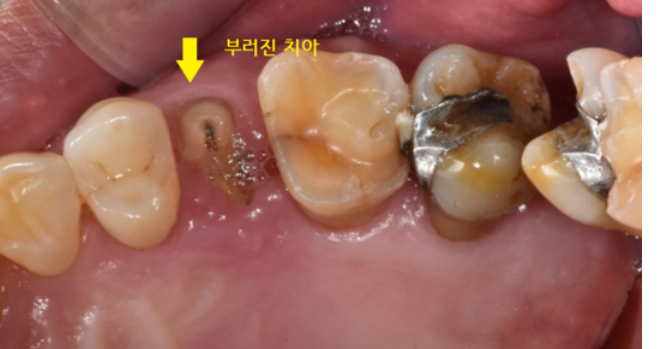

오늘의 환자분 치아가 부러져서 병원을 내원해주셨습니다.

치과 처음 내원하셨을 때 찍어놓은 사진입니다.

치아 부러짐 부위 딱! 보이죠~?

생각보다 많이 부러졌네요~

그 외에도 전반적으로 이가 많이 닳아있고

어금니를 덧댄 흔적도 보입니다.

한눈에 보기에도 뿌리만 남아있는 상태

부러진 부위가 머리 부분 대부분을 차지했습니다.

부러진 부분도 크고

신경치료도 되어있는 흔적이 보였습니다.